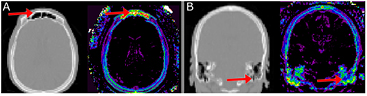

For the frontal sinus an LAC of 0 cm−1 was assigned for all voxels within the air mask regardless of the  signal. This choice was due to the

signal. This choice was due to the  signal in this area being purely noise (figure 4(A)).

signal in this area being purely noise (figure 4(A)).

Standard image High-resolution imageFigure 4. Complex air/tissue interface areas results in noisy  signal in (A) the frontal sinus and (B) the skull base. Left in each is CT, right shows the corresponding

signal in (A) the frontal sinus and (B) the skull base. Left in each is CT, right shows the corresponding  signal. The masks shown in figures 3(A)–(D) remedy these areas.

signal. The masks shown in figures 3(A)–(D) remedy these areas.